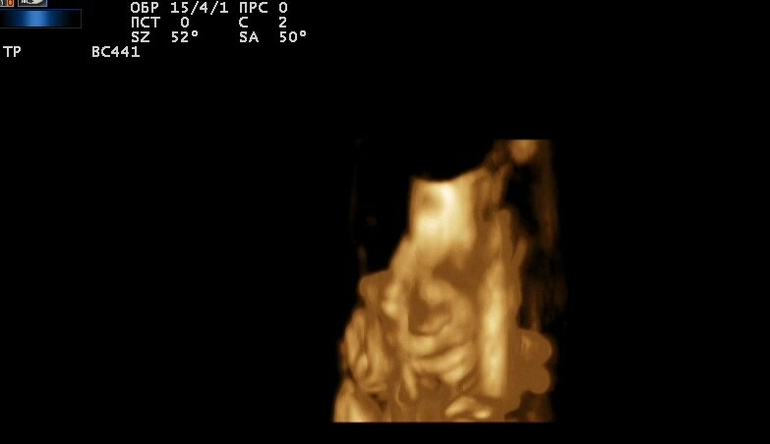

4д узи в 25 недель

УЗИ, КТГ, доплерДождалась я этого дня. Сначала сын прятал лицо руками,а потом начал пальчик сосать.

Я думаю все от аппарата зависит. Я бы хотела качество получше. Но одно поняла что снова на папу похож,это видно сразу. Еще видео записали там он пальчик сосал,все хорошо было видно.